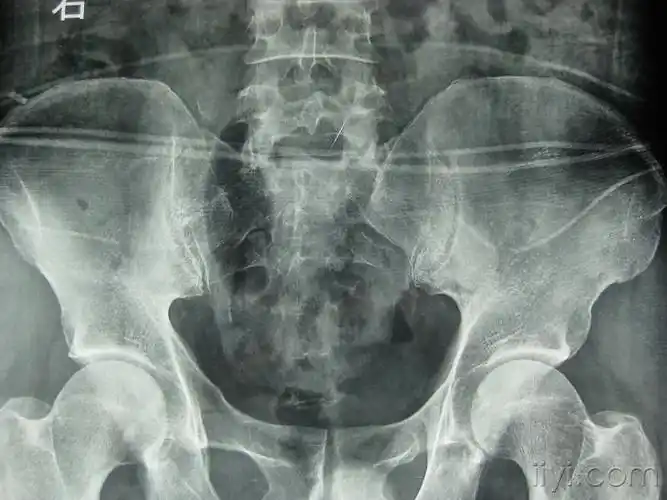

附病例(x线 ct):另外,骶尾骨骨折,特别是尾椎脱位的诊断还要和临床

有没有大神帮我看下这个片子尾椎骨疼痛拍片子医生说正常回家静养现在

尾椎骨骨折

尾骨骨折